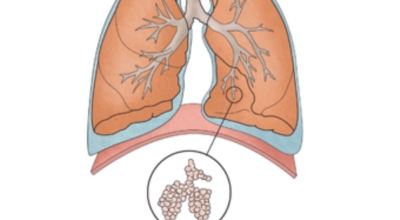

폐암이란

폐암은 폐에 생긴 악성 종양입니다. 폐 자체에 나타나는 원발성 폐암과 다른 장기에서 전이되어 온 전이성 폐암이 있습니다. 전 세계적으로 해마다 130만 명이나 되는 사람들이 폐암으로 사망하는데 이는 암에 의하여 사망하는 것 중에 가장 높은 비중을 차지하고 있습니다.